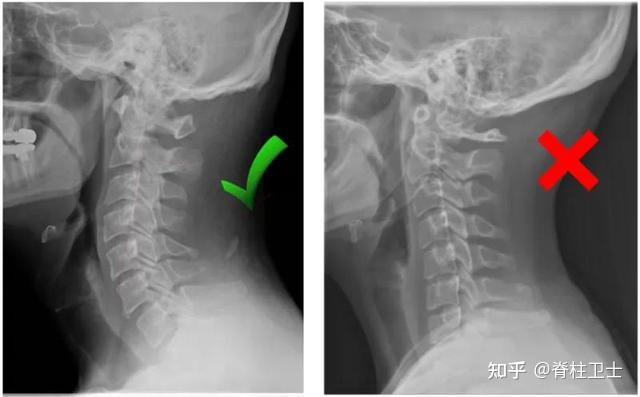

健康的頸椎都具有向前彎曲的c型曲線。但生活中長期的不良姿勢,卻十分容易導(dǎo)致頸椎出現(xiàn)骨性畸形

頸椎變直:頸椎的前凸C型弧度減小變直。

頸椎反弓:頸椎變直后繼續(xù)發(fā)展,變成后凸C型。

02_拍X片

到醫(yī)院拍個X片,能比較直觀地看到頸椎曲度的變化。